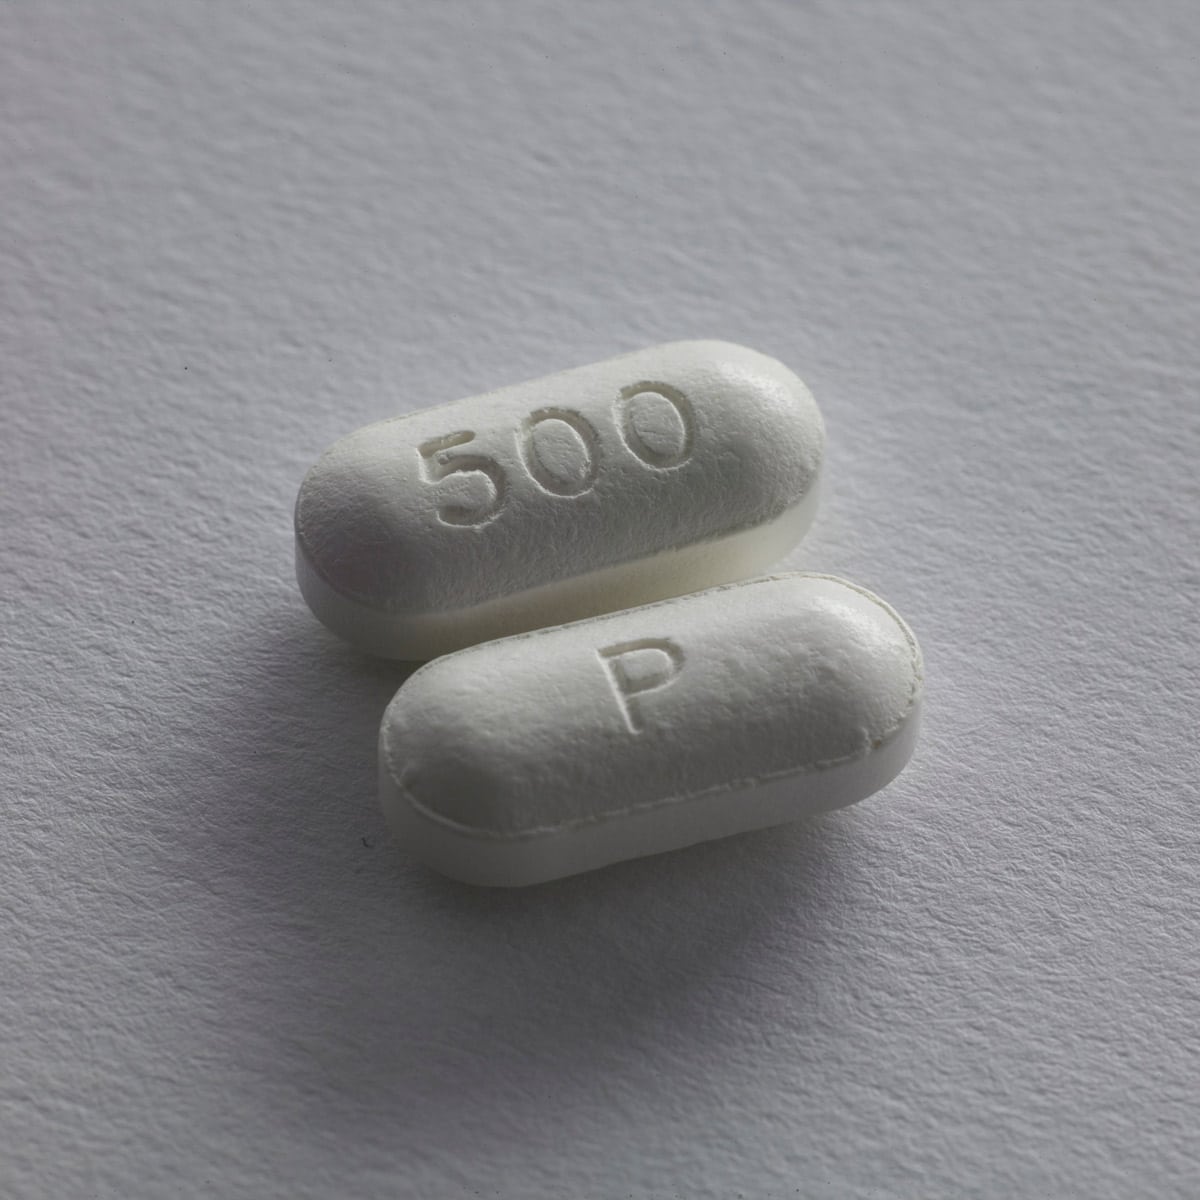

National Drug Take Back Day